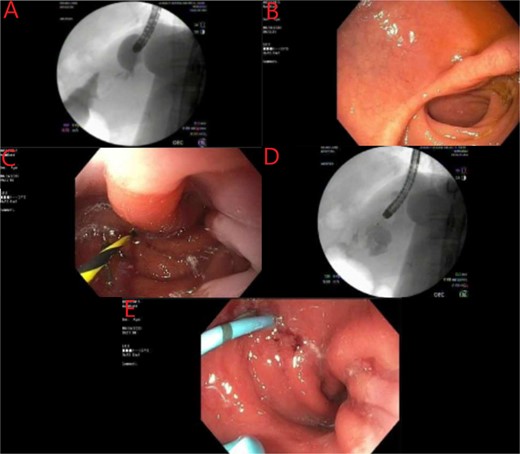

A multidisciplinary approach was applied for the complexity of this case. She was maintained on meropenem and she was receiving parenteral nutrition upon arrival to our center, as well as gastrointestinal prophylaxis with proton pump inhibitor and sucralfate therapy. The patient did not have a lactic acidosis or leukocytosis. Nutrition laboratory values were drawn, as shown in Table 1. Within 24 h the patient was brought to the endoscopy suite for luminal evaluation via esophagogastroduodenoscopy (EGD) and a transgastric stent was placed into the abscess cavity. The images from this study can be found in Fig. 2.

Endoscopic evaluation and stent placement into perforation of the gastric cardia. (A) Delayed imaging of UGI series with no extravasation of contrast. (B) Widely patent duodenal switch lumen. (C) Wire being placed into the fistula tract of the gastric cardia. (D) Contrast filling into the identified abscess cavity. (E) Placement of a double lumen stent through the fistula into the abscess cavity.